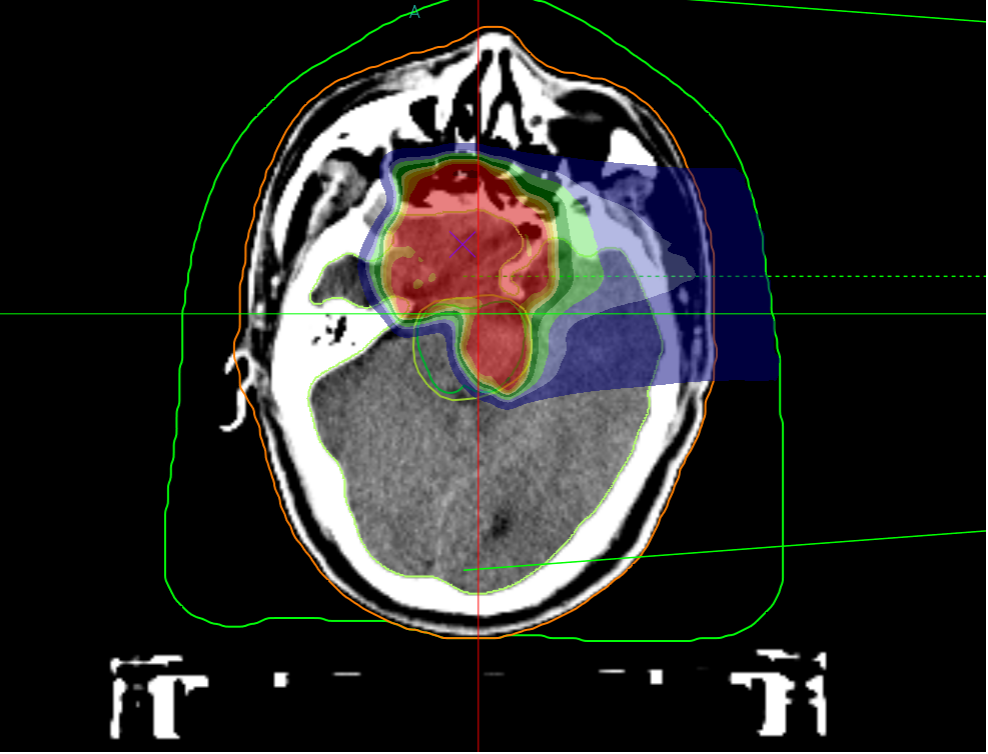

Carbon Ion Treatment Plan Dose Cloud Chart, Perfectly Protecting the Brainstem

Due to the special location of skull base chordomas, they often invade and compress the brainstem. Auntie Qiao's lesion protruded into the pons. Conventional photon radiotherapy and similar methods cannot protect the brainstem, whereas heavy ions have unique physical advantages enabling precise "targeting" of the tumor. The biological advantages of heavy ions have a good effect on radiation-resistant tumors like chordomas. Auntie Qiao's skull base chordoma with brainstem compression has been "cured."